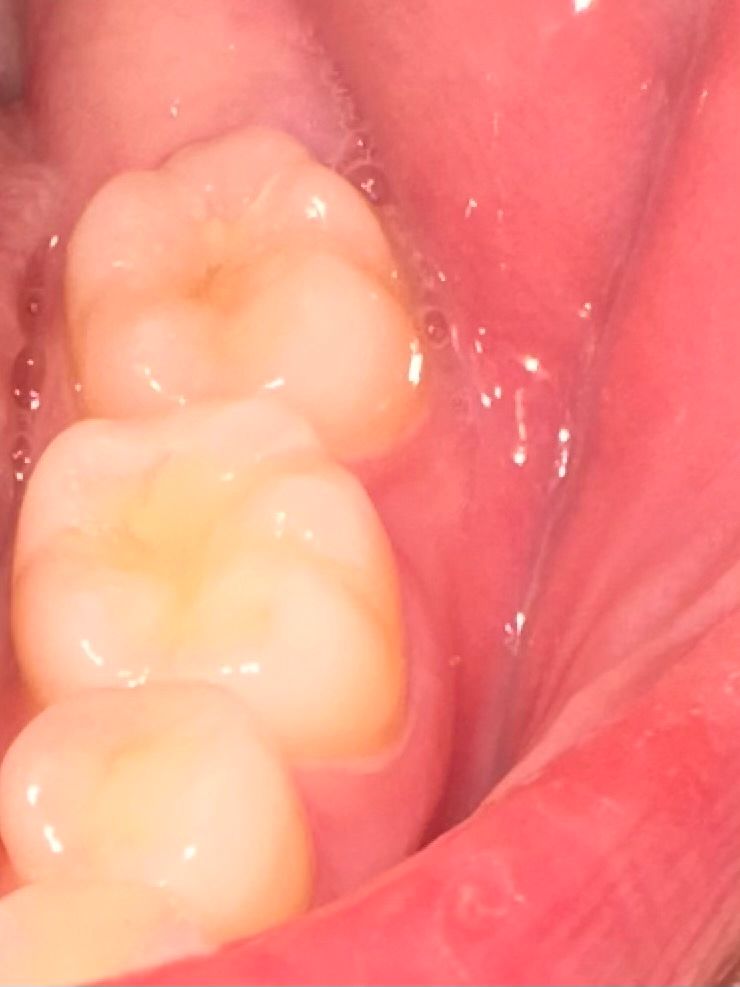

저기 맨 뒤 이빨입니다. 저번에도 이런적이 있어서 치과를 갔는데 충치는 없다고 하더라구요. 반년이상이 지나고 최근들어 또 뭔가 미세하게 시린 느낌이 나서,, 신경도 쓰여서 괜히 아픈 느낌이 들고 충치 맞나요? 맞으면 초기 인가요? 충치치료 아플까요?

• 2번 째 사진

사진에 보이는 부분에 잇몸이 안좋은거 같습니다. 일단은 잇몸치료를 먼저 받아보시는게 좋을것같습니다.

사진 상으로는 충치가 의심되지는 않습니다. 시린 증상 지속시엔 치과에서 검사 받아보시는 게 좋겠습니다.

사진으로만 봤을경우 크게 문제가 있는것으로 보이지는 않습니다 이런경우 치아에 너무 강한힘이 가해지는 것일 수도 있으니 치아에 가해지는 힘을 줄여주는 것이 좋습니다

외견상 충치은 없어보이고 단지 치태및 치석이 다소 끼어있으니 치과가서 스케일링 한번 받으시기 바랍니다